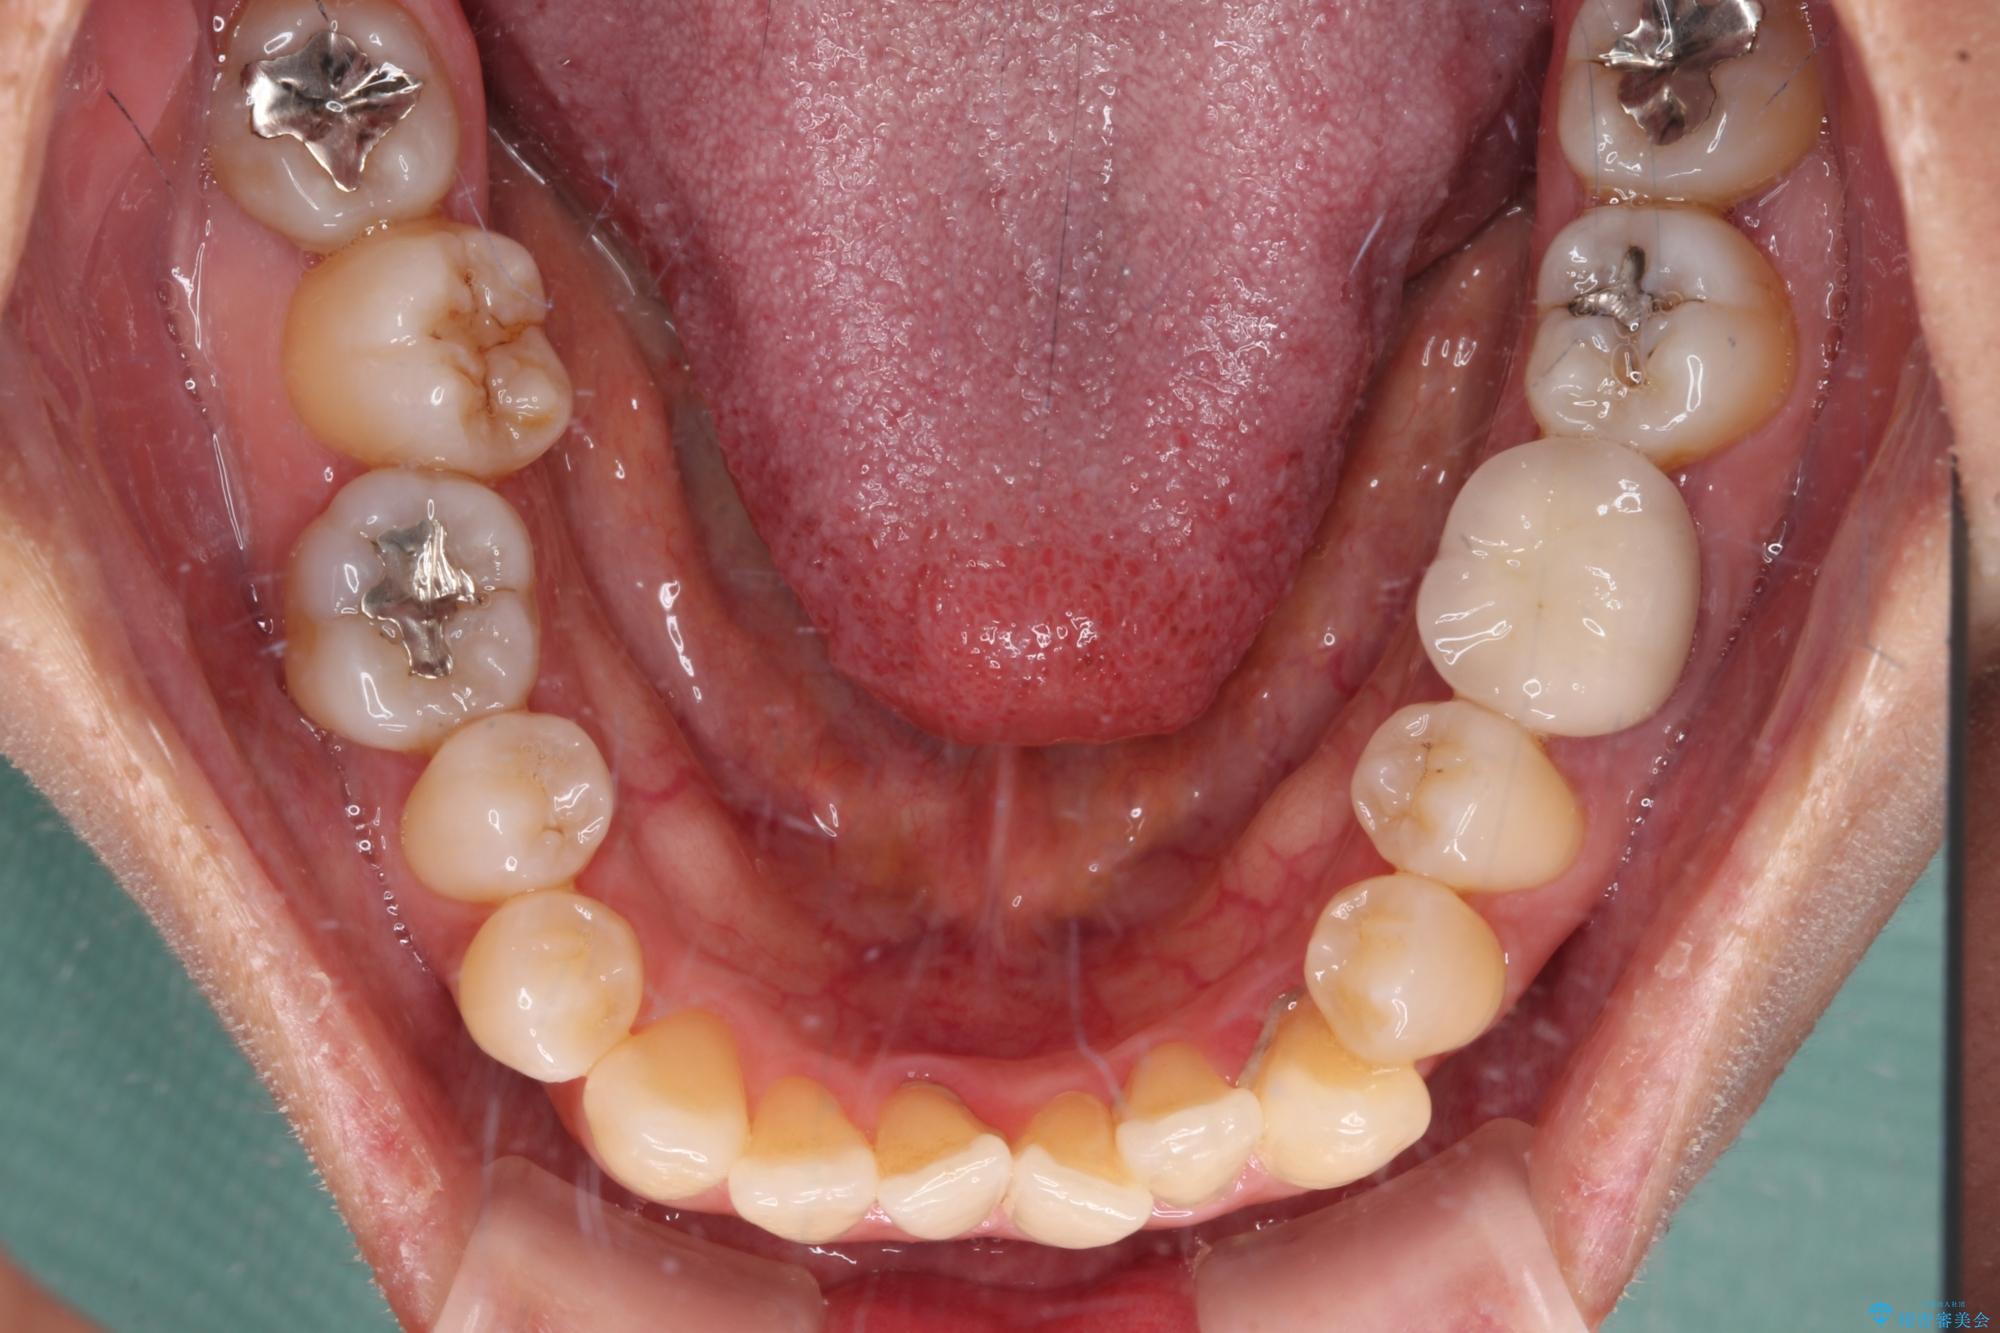

- 前歯のデコボコや八重歯を治したいとのことで来院された患者様です。

受け口傾向の骨格であり、前歯はクロスバイトまたは切端咬合となっており、下顎を中心に歯列全体の後方移動を行い、IPR(歯と歯の間を削る)によってデコボコが解消するように設計し、インビザラインにより治療を行うこととしました。

受け口傾向のインビザライン矯正は比較的治療を行いやすいため、きれいに仕上げることができました。舌の突出癖が顕著であったため、改善のためのトレーニングをしっかりと行っていただきました。